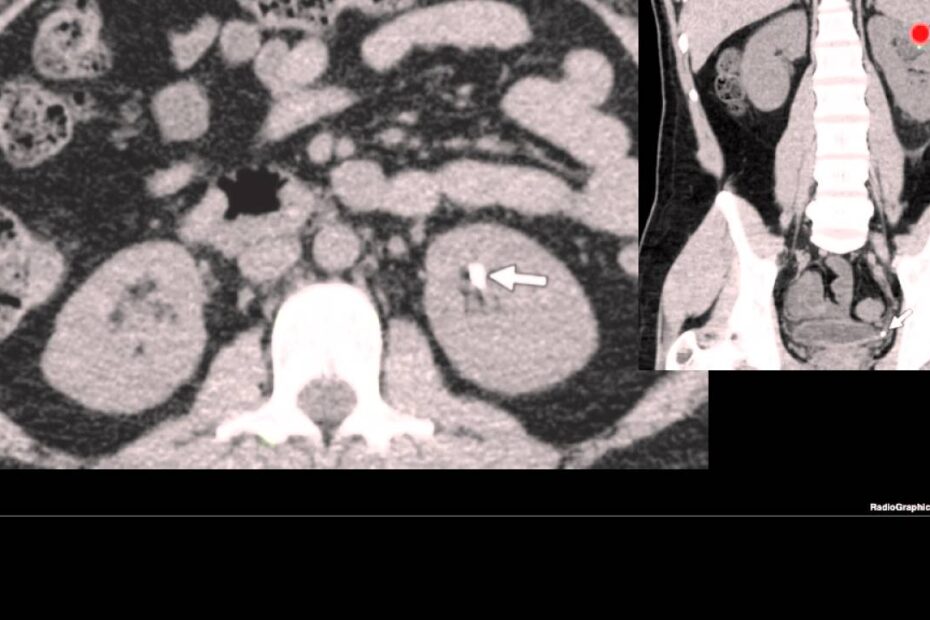

diagnóstico